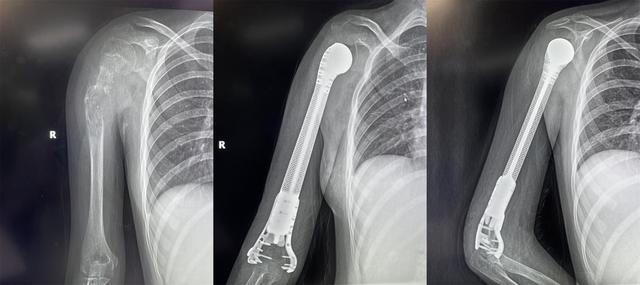

On April 19, 2022, the Department of Osteopathy and Oncology of Xi’an Honghui Hospital successfully performed resection of a humeral malignant tumor for a 13-year-old patient3D printingProsthetic reconstruction.

For a 13-year-old girl, amputation will inevitably bring a huge shadow to the child’s mind. At the same time, after Xiaoxin’s parents expressed their strong willingness to save the limb, they finally decided to choose the limb salvage plan. In response to Xiaoxin’s specific condition, Yang Tuanmin of the Department of Osteopathy and Oncology was appointed to lead the team members Wang Zhichou, Huang Guilin, Shao Yuxiong, Li Zhengzheng and other attending physicians. After careful case discussion, it was decided that after neoadjuvant chemotherapy, the right humerus bone tumor was surgically removed. .play3D printingexistorthopedicsField advantages, design individualized 3D printed titanium alloy prosthesis of upper humerus, combined with artificial shoulder joint technology, retain part of normal bone and length of affected limb, and realize humerus reconstruction.

Preoperatively, through precise computer-aided design, imaging data mirroring, and titanium alloy 3D printing, the 3D printed imitation bone trabecular end and osteotomy end of the prosthesis can fit perfectly, enabling bone ingrowth and achieving biological reconstruction. Effect. This preserves the joint and reduces the incidence of prosthesis loosening. At the same time, the void structure is conducive to soft tissue ingrowth. On the day of the operation, with the cooperation of the Department of Anesthesiology, Yang Tuanmin appointed the team to work closely and perform precise operations to complete a series of operations such as tumor resection, 3D printing prosthesis implantation, and soft tissue reconstruction. It took 3 hours to successfully complete the hospital’s first 3D-printed humeral prosthesis for the treatment of humeral osteosarcoma.